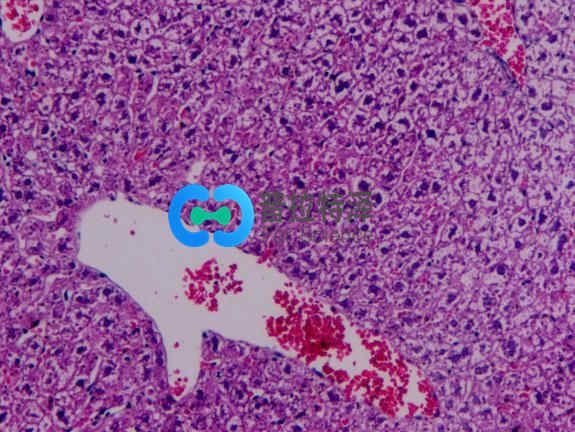

非酒精性脂肪性肝?。?/span>NAFLD)是一種無酒精濫用的肝病綜合征,包括單純性脂肪肝、脂肪性肝炎、脂肪性肝纖維化和肝硬變??蓮膯渭冃灾靖谓?jīng)非酒精性脂肪性肝炎(NASH)發(fā)展為肝纖維化,甚至導(dǎo)致肝硬化、肝細胞癌(HCC)或肝功能衰竭等終末期肝病。

動物模型在闡明非酒精性脂肪肝的病理生理機制以及新藥的開發(fā)中起著重要的作用。臨床前研究需要根據(jù)研究的特定NAFLD表型使用不同的動物模型。NAFLDNASH的臨床前動物模型可分為四類:飲食誘導(dǎo)模型、化學(xué)物質(zhì)誘導(dǎo)模型、基因編輯模型、復(fù)合模型。

給予動物高脂、高糖飼料喂養(yǎng)建立的脂肪肝模型,其主要發(fā)病機制是營養(yǎng)過剩,食物中脂類、膽固醇和(或)糖類過量,無法完全吸收利用,脂類堆積于肝而引發(fā)脂肪肝,進一步出現(xiàn)肝炎性改變及纖維化。該模型與人類NAFLD 相似,是最常見的NAFLD動物模型。不同的飲食誘導(dǎo)模型具有不同的特點。飲食誘導(dǎo)模型的一個挑戰(zhàn)可能是在開始研究之前需要較長的時間造模。

小劑量鏈脲佐菌素結(jié)合高脂飲食,已被用于制備小鼠的NAFLD,可導(dǎo)致脂肪變性,炎癥,纖維化甚至肝細胞癌。四氯化碳(CCl4)可造成肝損傷,可單獨施用或配合高脂飲食來誘發(fā)脂肪肝或肝纖維化。其機制主要是CCl4誘導(dǎo)肝臟發(fā)生氧化應(yīng)激反應(yīng),導(dǎo)致有害的脂質(zhì)和蛋白質(zhì)過氧化產(chǎn)物不斷產(chǎn)生和積累,并發(fā)生嚴重的壞死反應(yīng),從而導(dǎo)致肝細胞結(jié)構(gòu)和功能破壞。這種方法造模時間較短,但是發(fā)病機制、病程變化及組織學(xué)形態(tài)與人類脂肪肝存在較大差異,并且藥物毒性強,易致動物死亡。